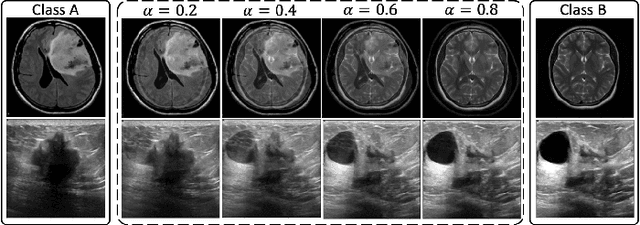

Abstract:Machine learning (ML) models are becoming integral in healthcare technologies, presenting a critical need for formal assurance to validate their safety, fairness, robustness, and trustworthiness. These models are inherently prone to errors, potentially posing serious risks to patient health and could even cause irreparable harm. Traditional software assurance techniques rely on fixed code and do not directly apply to ML models since these algorithms are adaptable and learn from curated datasets through a training process. However, adapting established principles, such as boundary testing using synthetic test data can effectively bridge this gap. To this end, we present a novel technique called Mix-Up Boundary Analysis (MUBA) that facilitates evaluating image classifiers in terms of prediction fairness. We evaluated MUBA for two important medical imaging tasks -- brain tumour classification and breast cancer classification -- and achieved promising results. This research aims to showcase the importance of adapting traditional assurance principles for assessing ML models to enhance the safety and reliability of healthcare technologies. To facilitate future research, we plan to publicly release our code for MUBA.